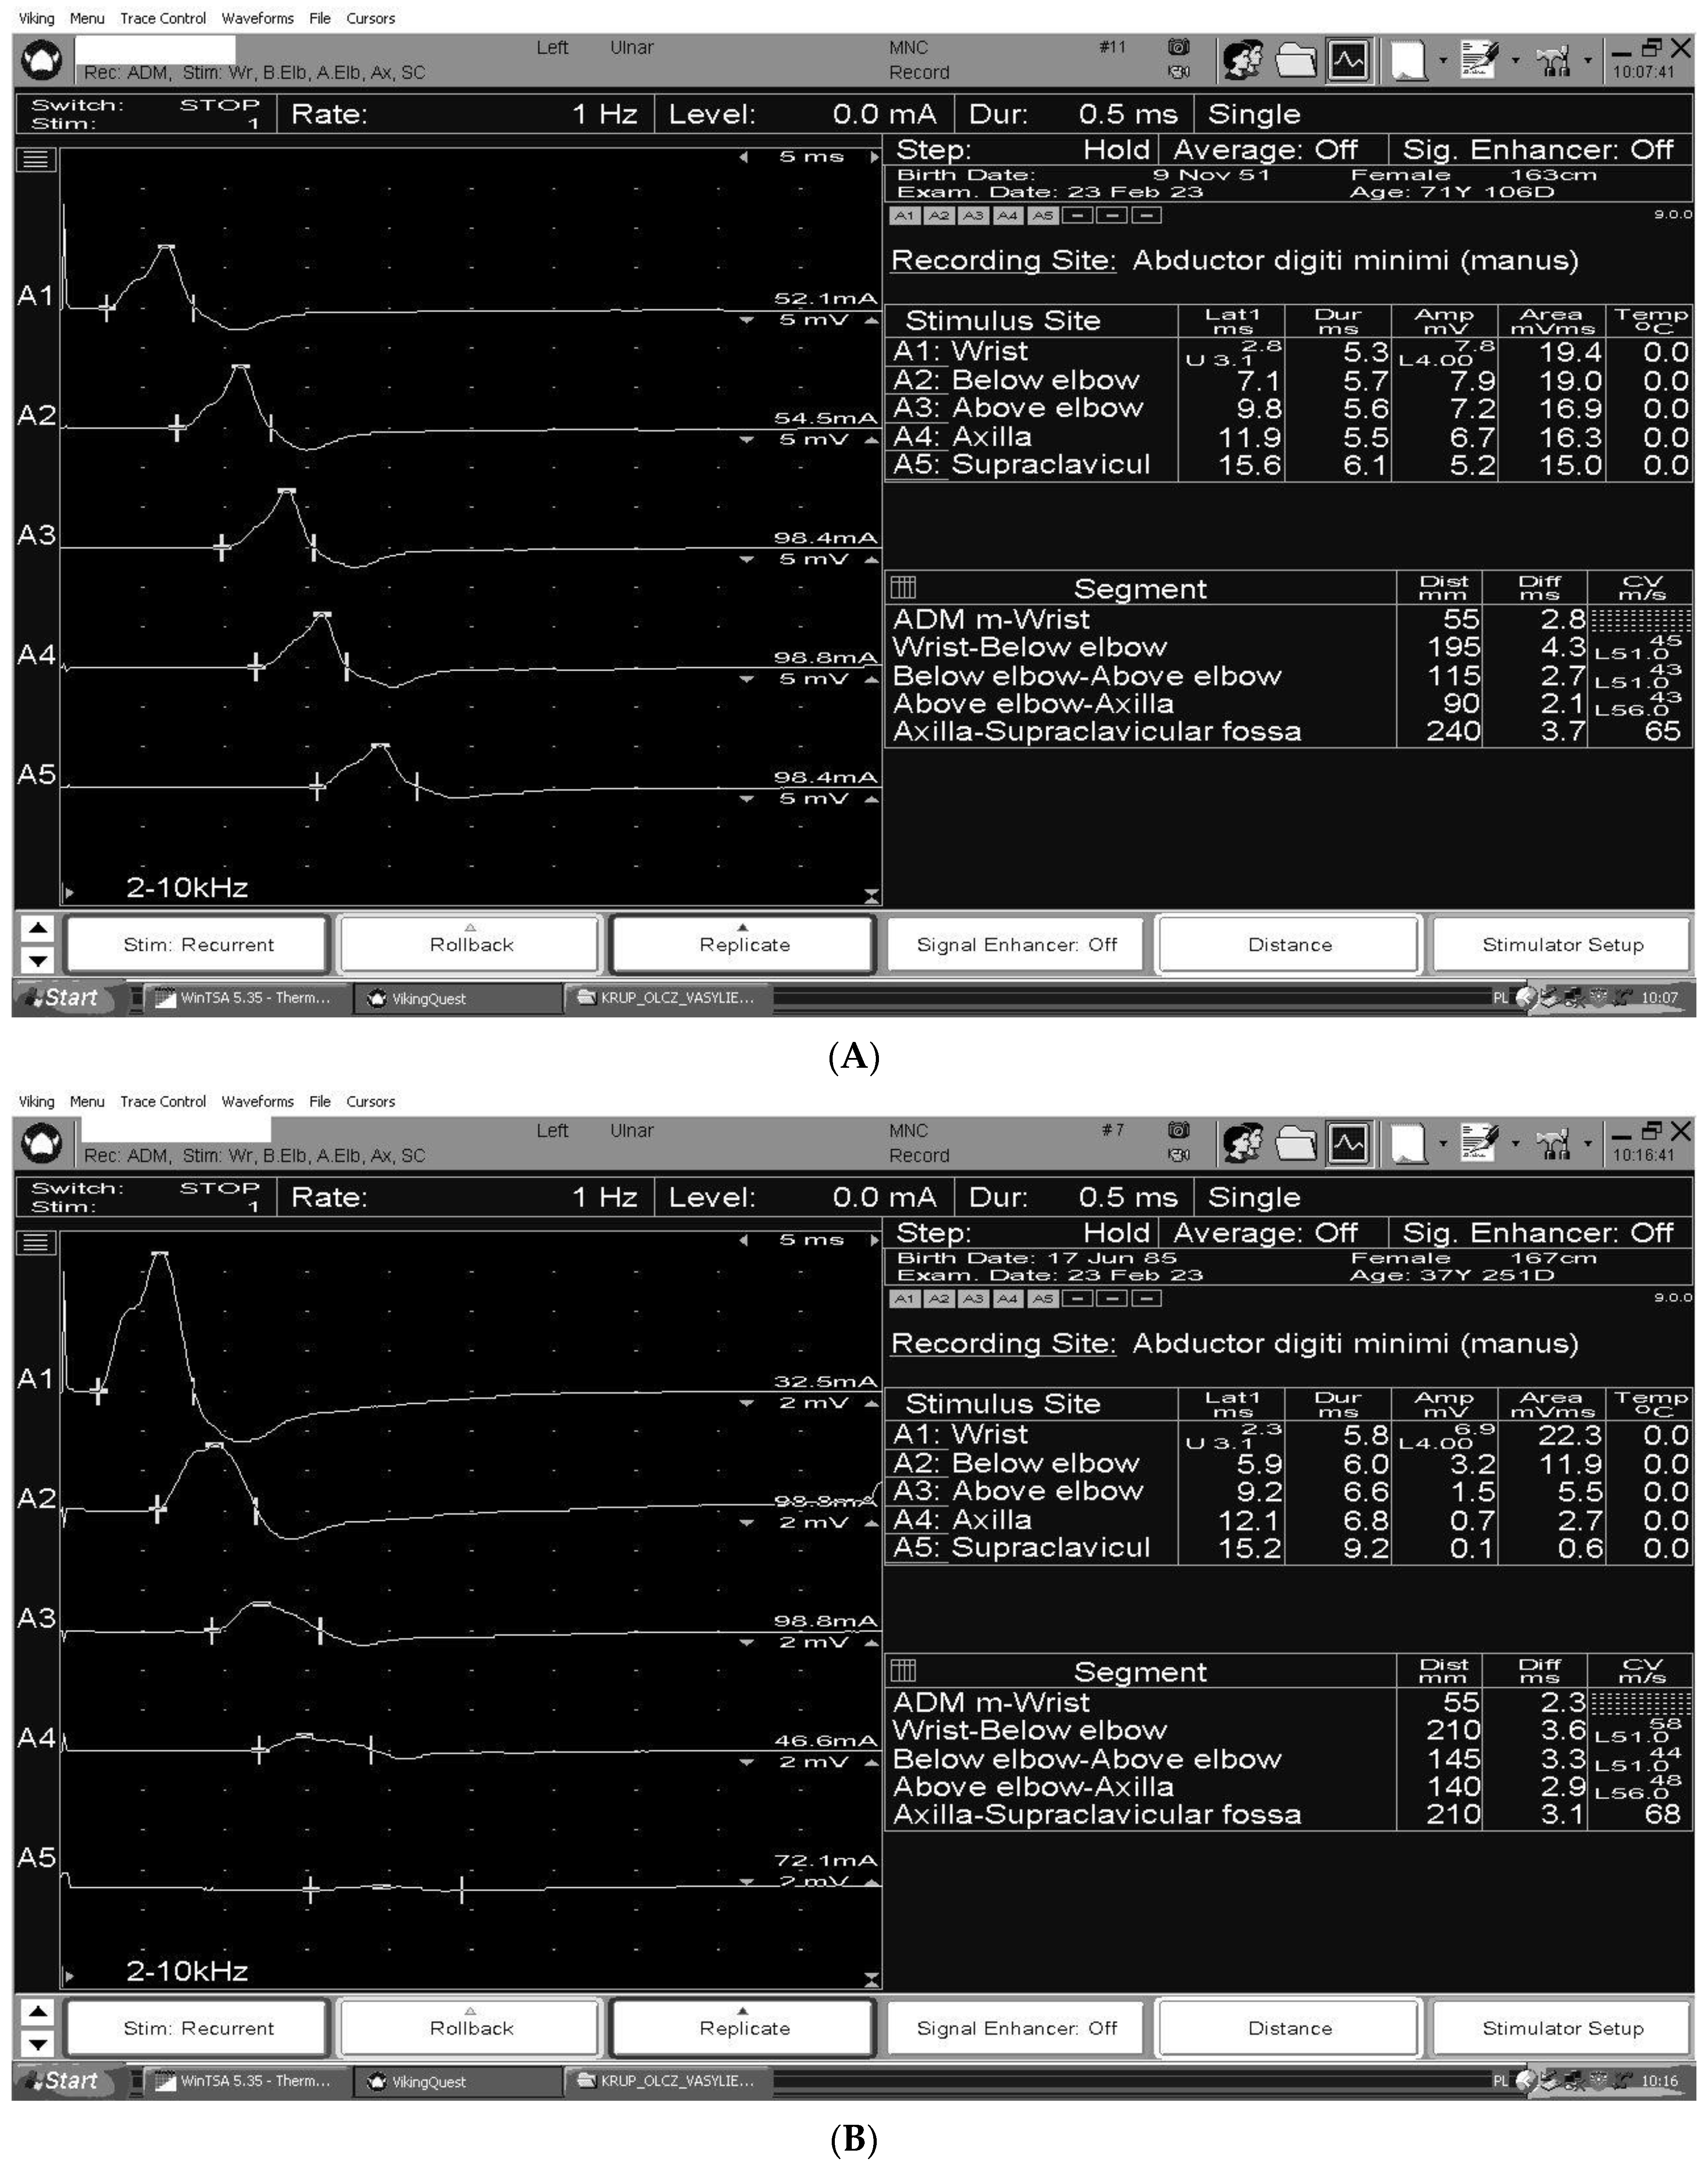

3. The Electrodiagnosis